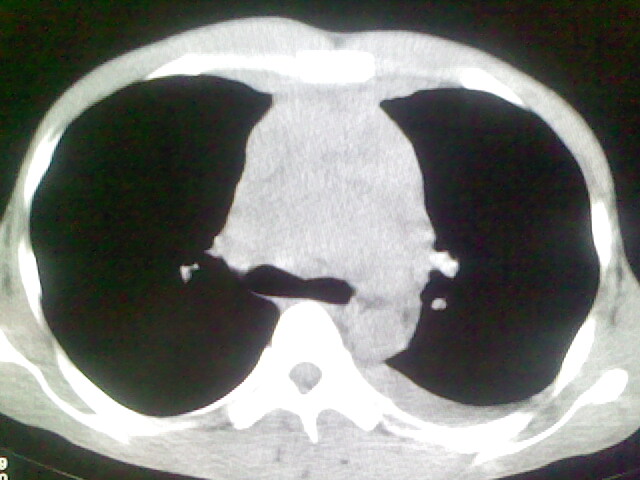

以下是引用杀毒软件在2008-9-3 6:11:00的发言:[br]侵袭性胸腺瘤------一般不侵到气管旁[br][br]考虑----纵隔淋巴瘤,心包及胸膜受累

以下是引用wzr在2008-9-3 5:30:00的发言:[br]侵袭性胸腺瘤

以下是引用随光逐影在2008-9-3 7:07:00的发言:[br]1)考虑淋巴瘤可能。2)双侧胸腔积液(以左侧为甚)。3)心包积液。